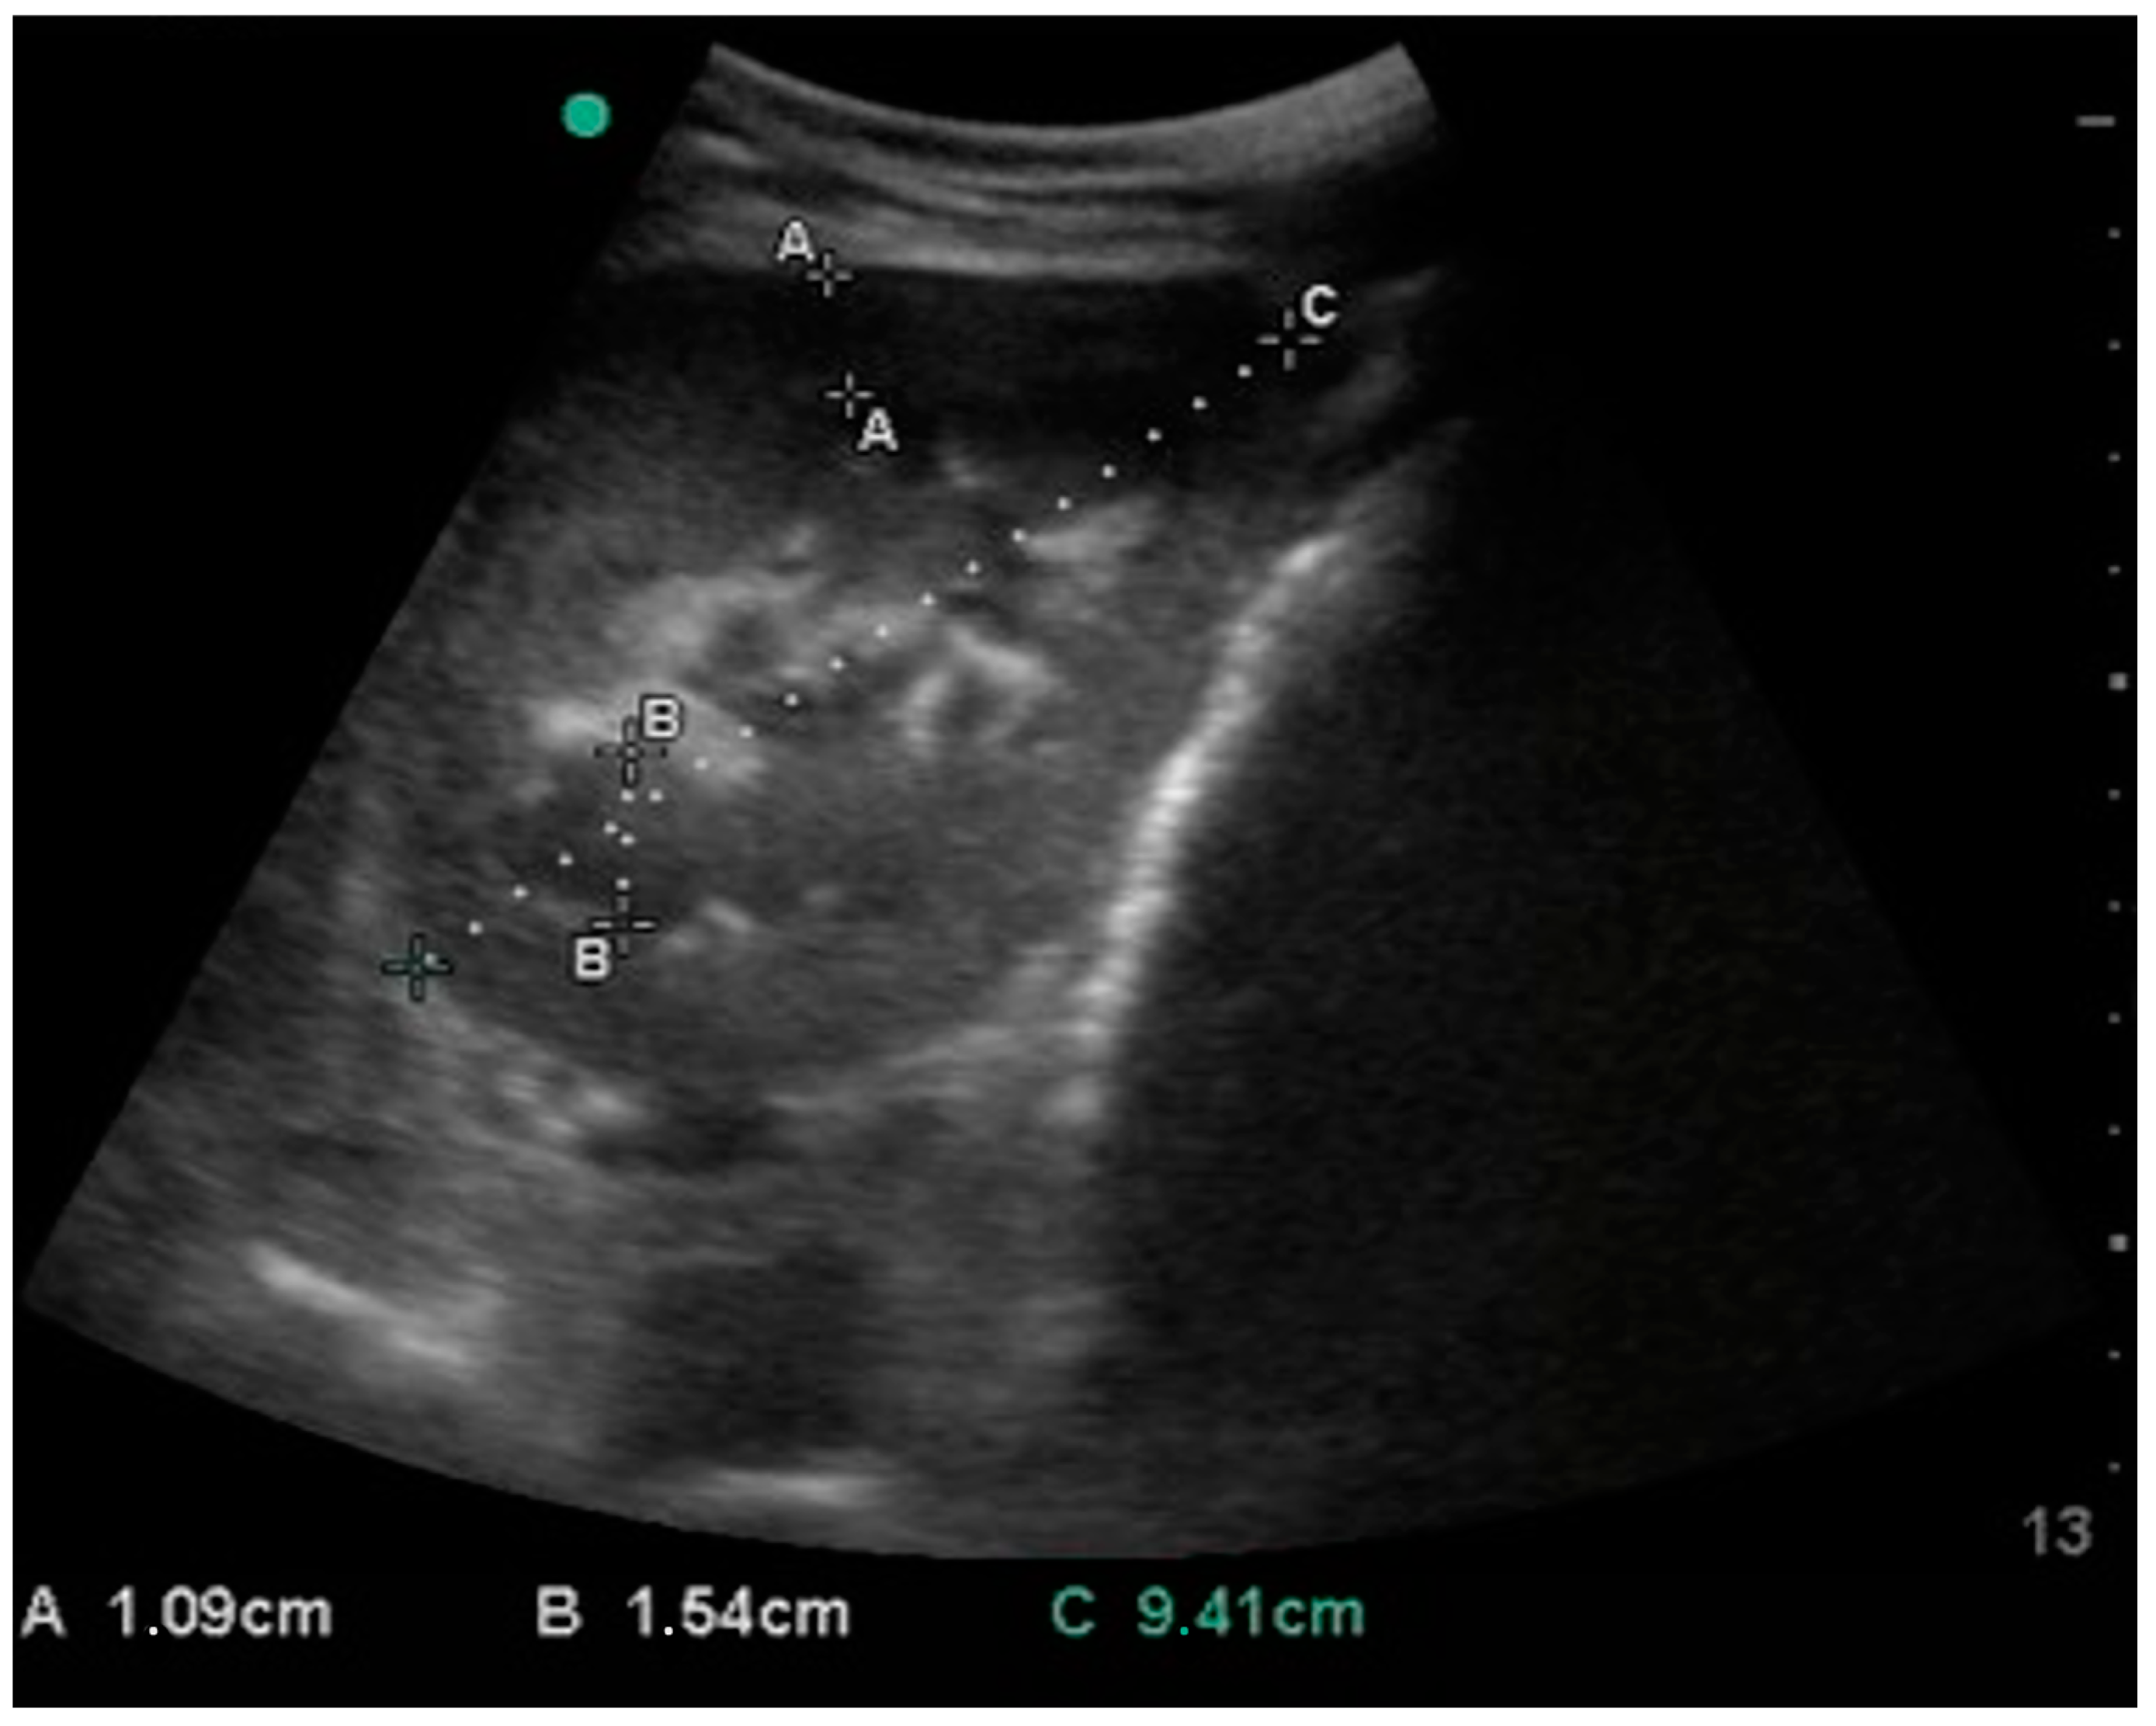

3. Results

| Left kidney | length | 91.5 (9.0) | 88.0–96.8 | 84.6 | 88.7 | 96.5 | 99.0 | 66.3 | 108.0 | 41.7 |

| cortex | 8.4 (2.2) | 6.7–8.9 | 6.3 | 6.9 | 8.9 | 10.9 | 5.3 | 13.9 | 8.6 | |

| medulla | 15.6 (5.5) | 11.6–17.0 | 10.1 | 11.4 | 18.8 | 22.5 | 8.0 | 27.4 | 19.4 | |

| Right kidney | length | 95.5 (10.8) | 88.1–98.7 | 82.6 | 89.8 | 102.3 | 110.0 | 77.5 | 113.0 | 35.5 |

| cortex | 8.4 (1.6) | 7.7–9.3 | 6.4 | 7.5 | 9.6 | 10.4 | 5.8 | 11.4 | 5.6 | |

| medulla | 15.3 (2.0) | 14.1–16.1 | 13.1 | 14.8 | 16.8 | 17.2 | 10.5 | 18.8 | 8.3 | |